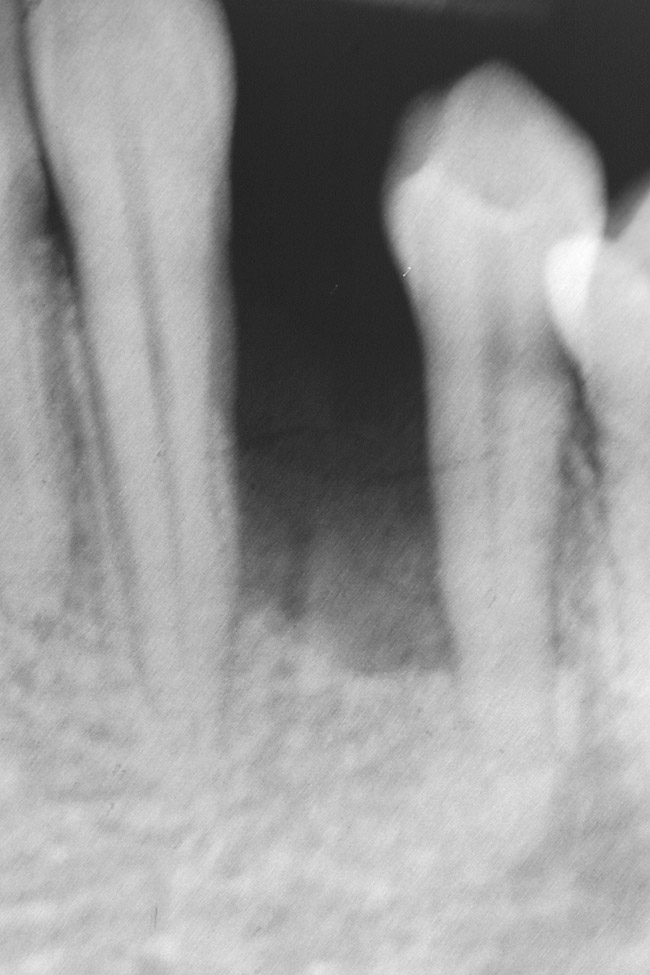

Figure 7  Radiograph of residual ridge defect in site No. 22.

Figure 7